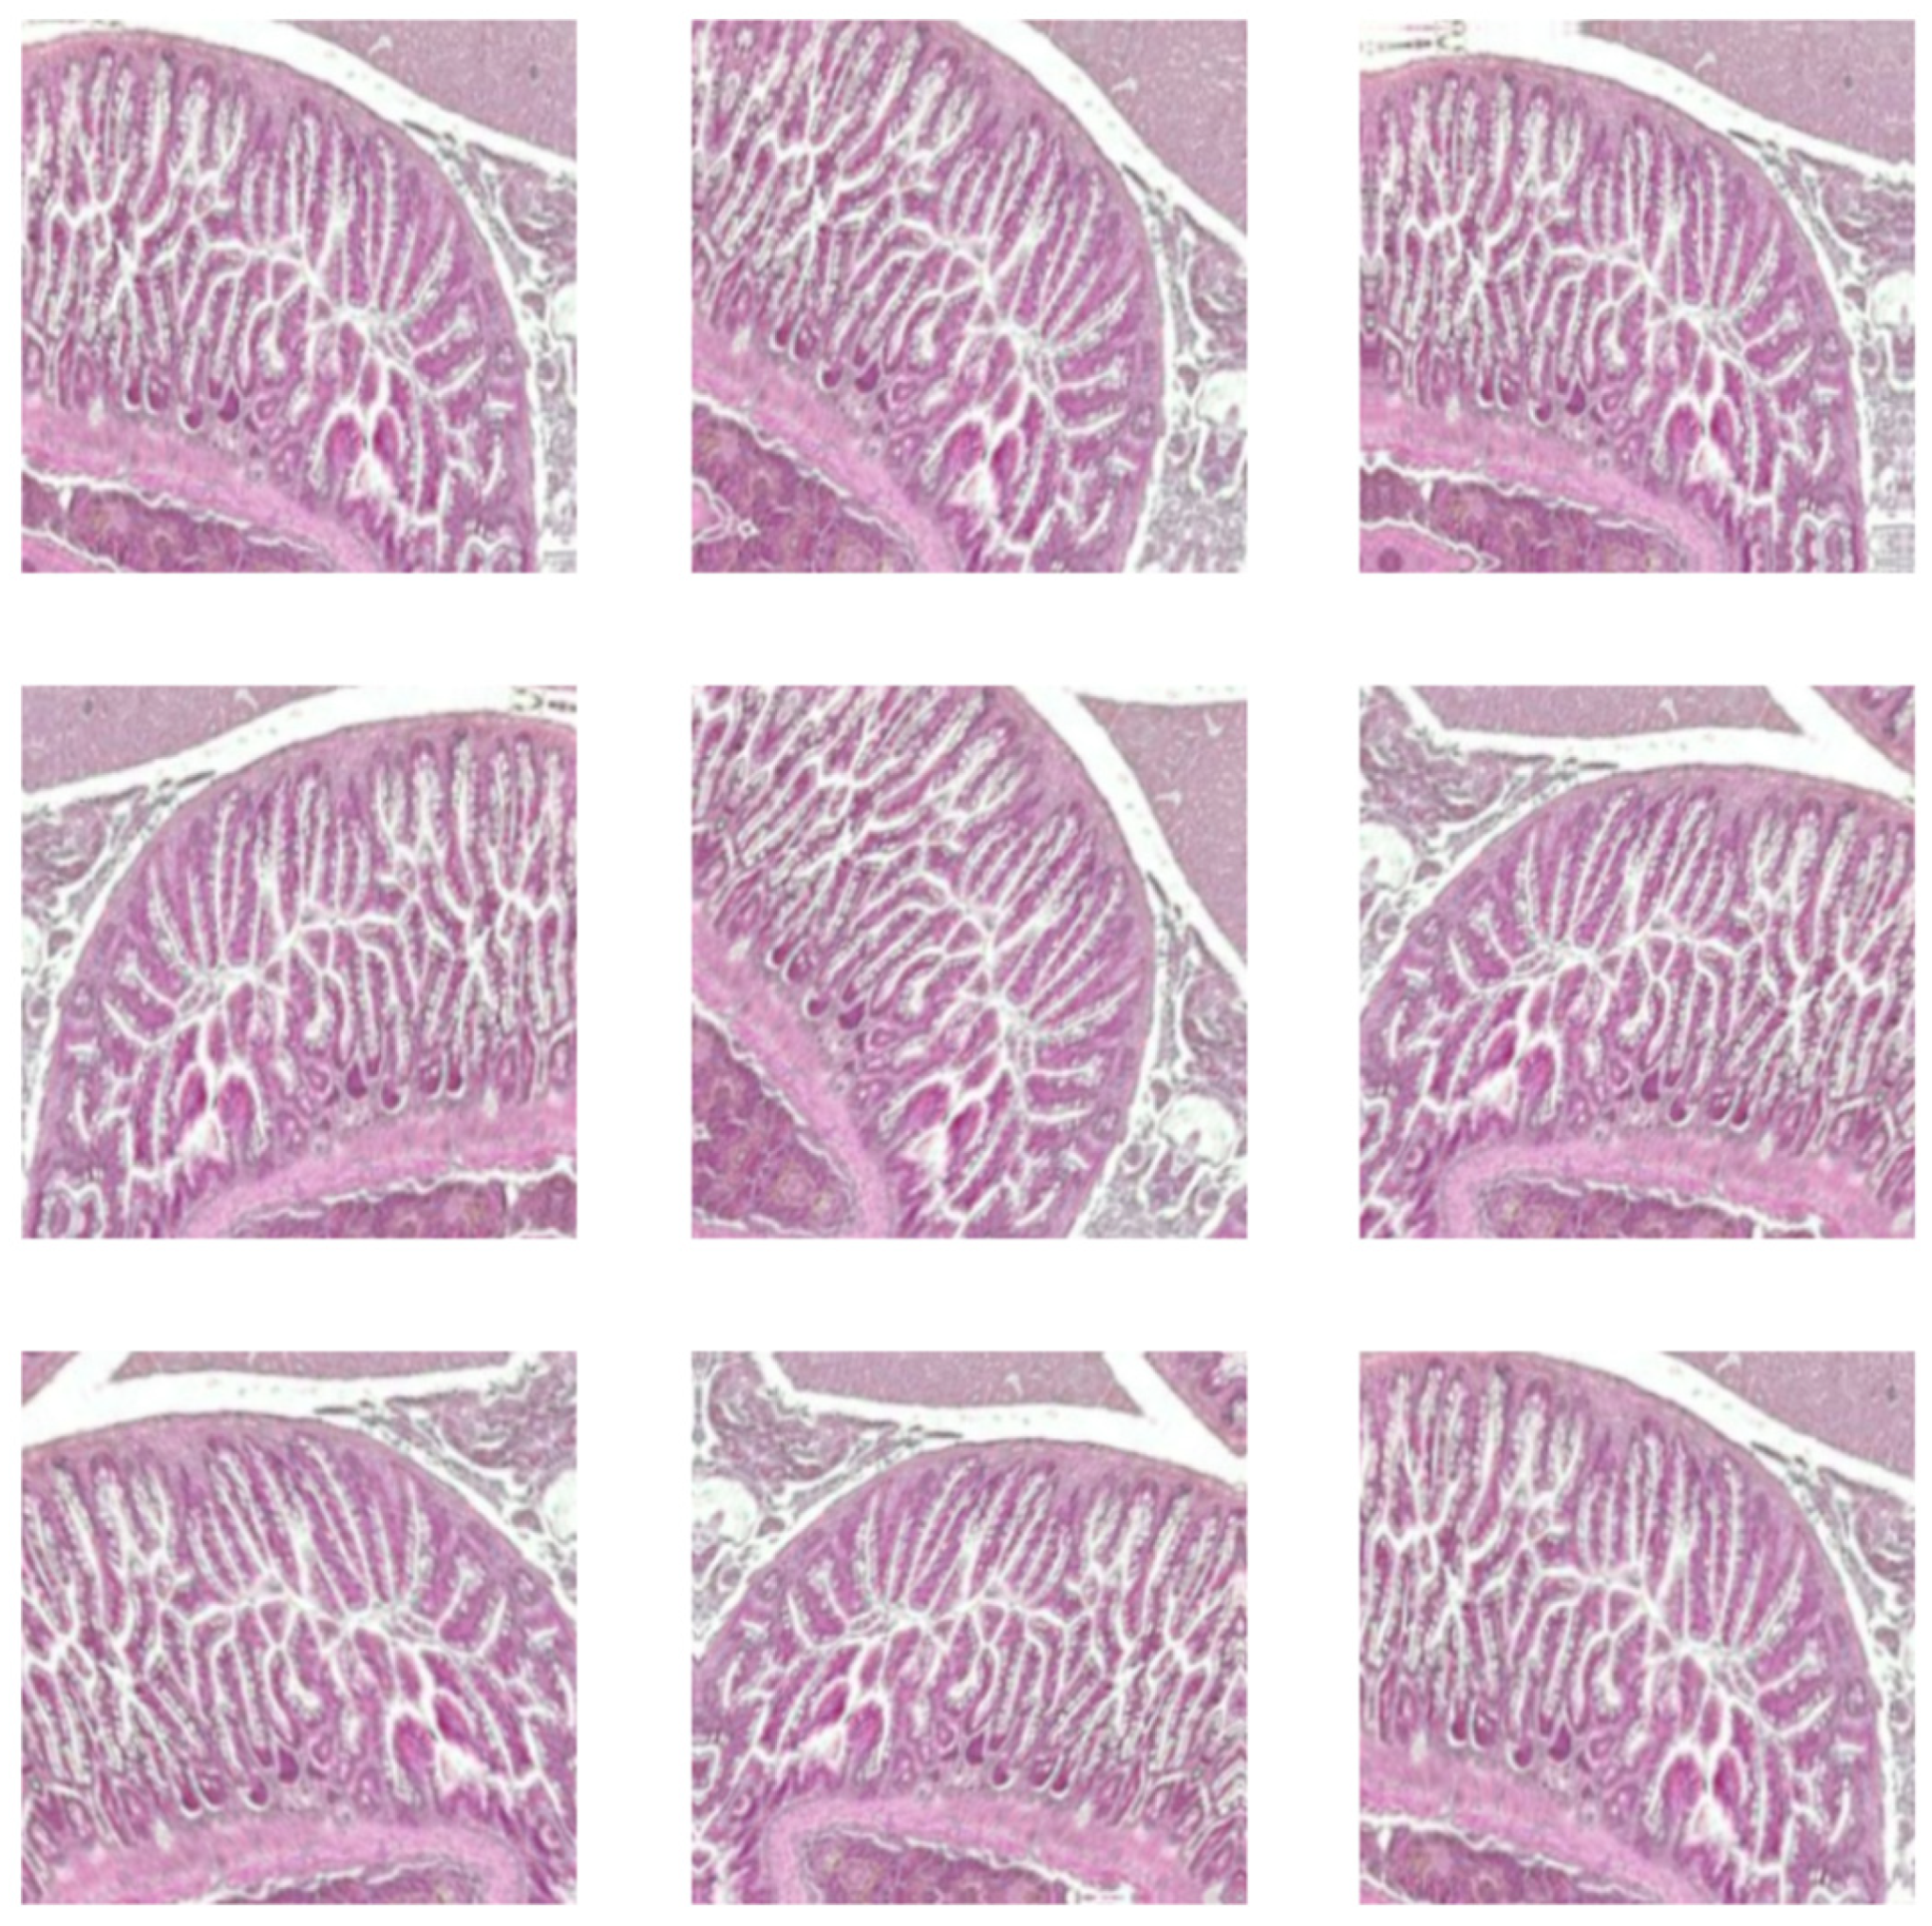

The augmentation incorporates random rotations up to 10 degrees, random zooms with 10% interpolated pixels, and random horizontal flips with a 10% probability. A sample of augmentation in Figure 3 is shown. This technique was applied to the training dataset, which included both raw images and images that were pre-processed using the CLAHE method. It was necessary because it enhanced the DL model’s ability to generalize by introducing variability in the training data. As a result, the model becomes more robust and for classification intestine histological images.

Figure 3. Augmented intestine histological images.